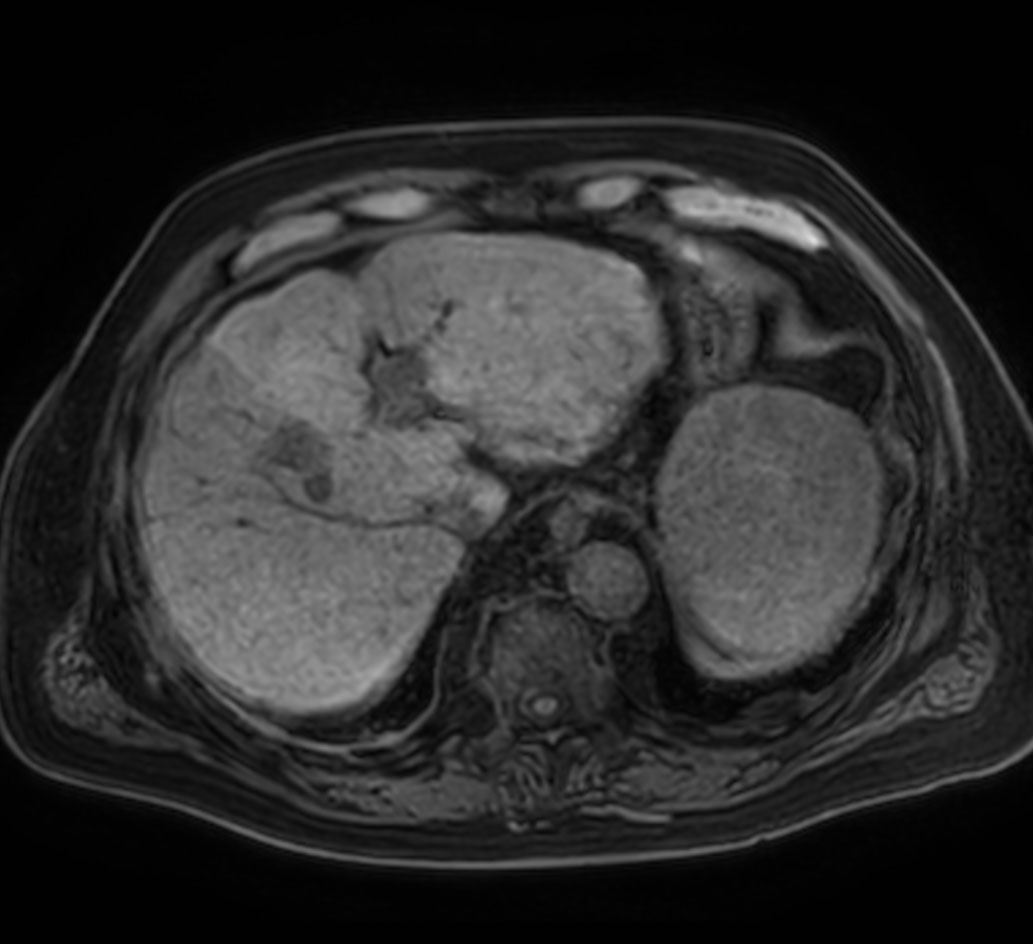

Axial T1w mDIXON XD (In Phase)